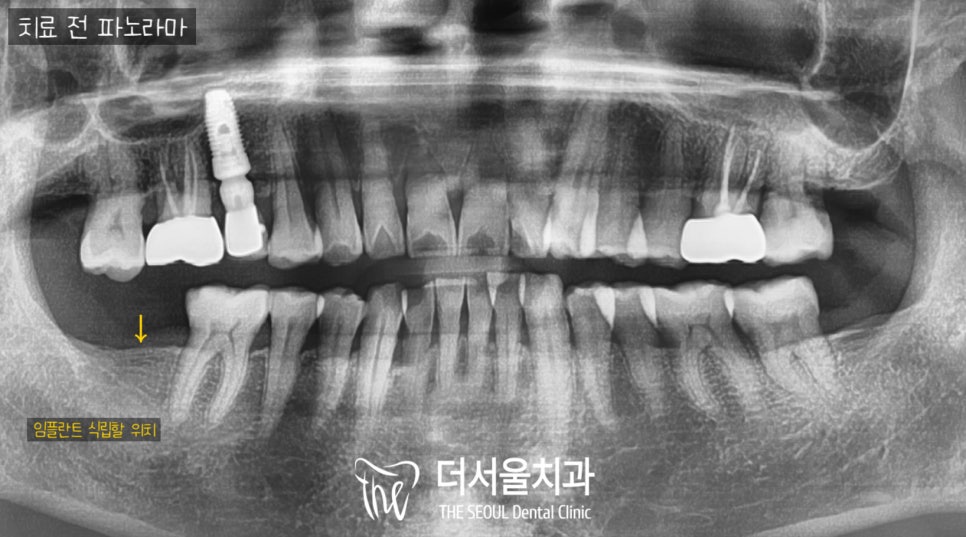

1. 초진

이 환자께서 이미 오래전에 이가 빠진 채로

보험 implant를 하러 내원하셨어요.

2. 디지털 임플란트 프로그램 분석

저희 장지동 치과 에 디지털 임플란트 는

뼈의 단면 및 신경관, sinus의 위치를

데이터 기반으로

어디에 심겨야 좋은지를

분석 및 판단하여

진행 전 미리 그 예후를 확인할 수 있습니다.

사진을 살펴보면 골밀도가 낮기는 하나

뼈의 폭과 두께, 잇몸상태가 양호하여

무절개 방식으로 계획을 수립하고

무통마취 후 바로 수술에 들어갔습니다.